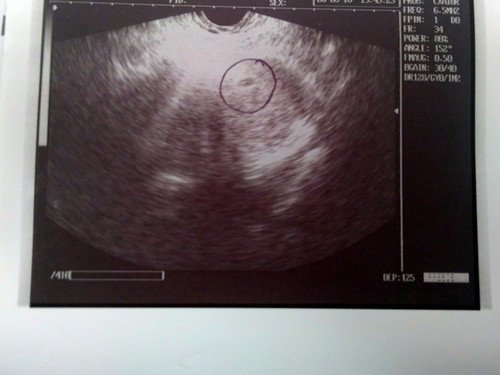

5 Weeks preggy ako as estimated. We went to my OB for prenatal checkup. Aside sa niresetahan ako ng mga vitamins ay ni-check nya din kung may laman o may makikita na through an ultrasound scan. At base sa result, may nakita naman. Pero May nakapag sabi kasi na masama daw yung ultrasound scan sa ganitong stage kasi sobrang aga. Dapat daw transv. Can anyone enlighten me please? Totoo ba yun?